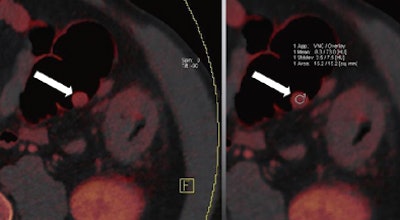

| Images are of a 65-year-old male patient who underwent a single acquisition at dual-source CTC. Above, a stenosing carcinoma was seen in the proximal sigmoid colon in 3D endoluminal views (left, middle) and 2D view (right). Below, an 18-mm colorectal adenoma was also found in the proximal sigmoid colon, and also appears to be enhancing. Bottom image shows an enhancing liver metastasis in the same patient. Virtual unenhanced (grayscale) images are created by electronically subtracting the contrast media. All images courtesy of Dr. Anno Graser. |

The technique can be used to determine the contrast media uptake of the polyp, as well as the baseline density of the lesion, directly measuring enhancement in HU and measuring the iodine in the lesion in grams per mL.